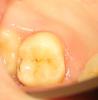

METT Опубликовано 27 марта, 2013 Автор Поделиться Опубликовано 27 марта, 2013 Фиксация вкладки на 16 1 Ссылка на комментарий

METT Опубликовано 27 марта, 2013 Автор Поделиться Опубликовано 27 марта, 2013 Пломбочка на 17 и покраска пломбы на 47 Ссылка на комментарий